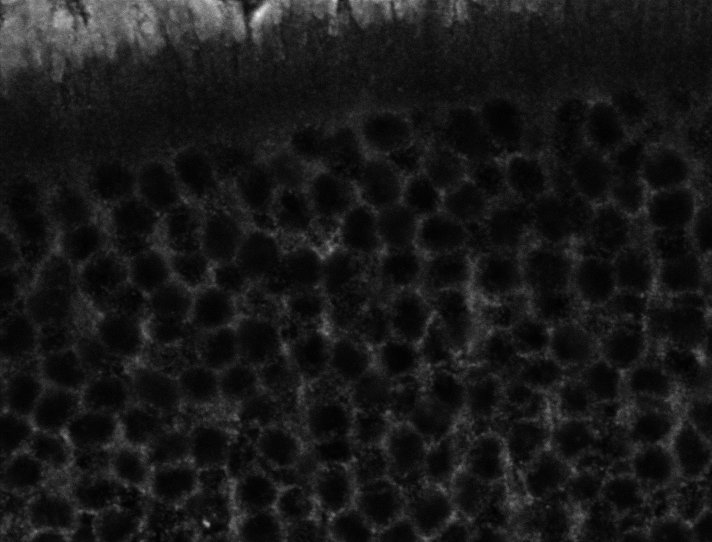

Tubulin - Bip

Tubulin - Nuc